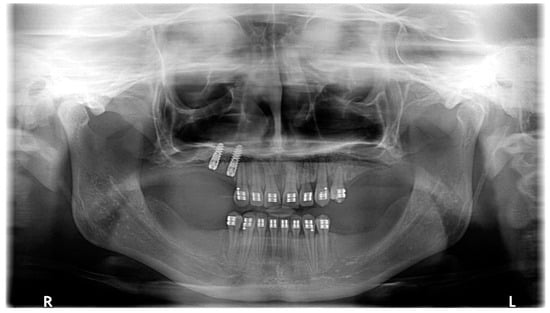

| March 2020 | The correct position of UL3; tooth no. 24 showed significant mobility; control panoramic X-ray: root resorption of tooth no. 24 (Figure 7); no possibility to conduct control visits on a regular basis due to COVID-19 pandemic—next appointment took place in November 2020. |

| November 2020 | 0.019″ × 0.025″ SS wire, torque expression, closure of spaces with power chain. |

| March 2021 | Removal of MIs, 0.021″ × 0.025″ TMA wire for torque expression in the upper arch; Fixed lower SS appliance Dentaurum Equilibrium® 2 0.022″ in Roth prescription (Dentaurum, Ispringen, Germany); 0.016″ NiTi wire; elastics 4 ½ oz. from palatal buttons on teeth no. 12 and 22 to the lower arch to correct the anterior crossbite (Figure 6l). |

| April–June 2021 | Further alignment of the lower teeth by means 0.017″ × 0.025″ NiTi, and next 0.019″ × 0.025″ SS; intermaxillary elastics 4 ½ oz and offset bends on teeth no. 12 and 22 were used to correct the anterior crossbite; elastic power chains for space closure. |

| August 2021 | Open sinus lift surgery with porcine bone-derived grafting material (The Graft™ bone substitute cancellous granules (Purgo Biologics, Seongnam, Republic of Korea) and BioCover™ resorbable collagen membrane (Purgo Biologics, Seongnam, Republic of Korea)) was performed on the right side of the maxilla. |

| March 2022 | Two dental implants were placed: tooth no. 14—Axiom® PX 3.4 × 12 mm (Anthogyr, Sallanches, France), tooth no. 15—Axiom® PX 3.4 × 10 mm (Anthogyr, Sallanches, France). |

| May–August 2022 | Finishing; control panoramic X-ray (Figure 8); 1st canine relationships and midline consistency; debonding of the brackets; fixed upper and lower retainers’ placement (0.027″ × 0.011″ 8-strand braided SS), tooth no. 24 was not fixed to the retainer due to increased mobility. |

| September 2022 | E-max (lithium desilicated ceramic) veneers on upper teeth; individual implant abutments (titanium pre-milled abutments) and implant-supported blocked crowns (zirconia veneered with porcelain using the cut-back technique) on dental implants; removable thermoformable retainer. |

| March 2023 | Retention phase: 10-month follow-up. Stability of treatment results; minimal opening of the spaces mesially to teeth no. 34 and 44; proper mobility of tooth no. 24. Bleaching of the lower teeth. |